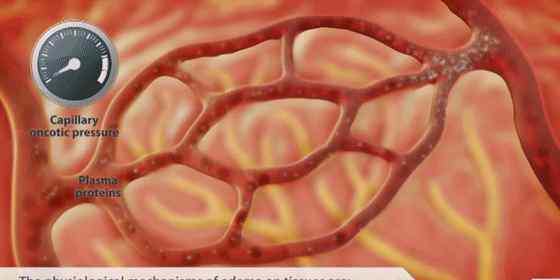

降低肌酐,最关键的只有一点,你是否已经认识到?血清肌酐的形成分为两部分,内源性肌酐主要是肌肉的代谢产物,外源性肌酐主要是吃肉后产生的。肌酐本身就是体内的一种垃圾。正常情况下,会被肾脏过滤后排出体外,达到平衡。但肾功能受损时,过滤能力下降,产生的肌酐不能及时排出体外,导致蓄积,血清肌酐的检测会增加。